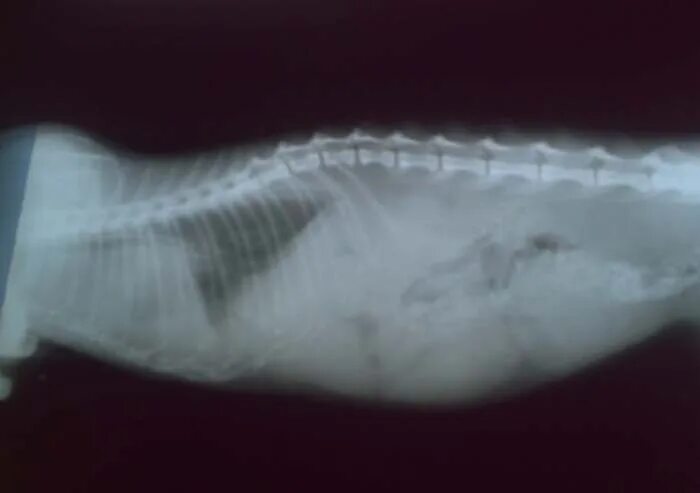

У кошки увеличены